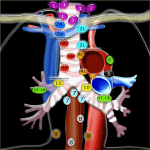

Hạch Trung Thất | Bài giảng CĐHA

* Nhóm 1: hạch cổ thấp, thượng đòn, hõm ức

– Bên phải và bên trái khí quản

– Giới hạn trên: bờ dưới sụn thanh quản

– Giới hạn dưới: xương đòn và bờ trên cán xương ức…